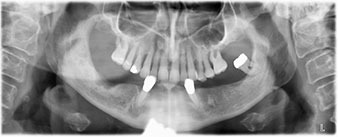

The 64-year-old patient presented with residual dentition of teeth 38, 33 and 43 and a clasp denture in the mandible (Fig. 1 and 2).

Following an explanation of the various treatment options open to her, the patient decided on extraction of the residual dentition in the mandible, an immediate implantation and treatment with the Fast & Fixed method (bredent medical), whereby the provisional fixed denture is screwed onto four implants on the same day as the surgery. The goal was to operate on the patient on the Friday so that she could assist in the oral examinations on the following Monday.

A three-dimensional cone beam computed tomography scan (CBCT, Planmeca) was performed to aid planning and minimize risks. This revealed that the quality and quantity of the available bone were sufficient for the surgery and immediate restoration using the Fast & Fixed method. Following the protocol for this concept, the implants are inserted at 35, 32, 42 and 45. Angling the distal implants by up to 45° shifts the emergence profile to posterior and generates a larger support polygon (Fig. 3).

The light increases the contrast in the oral cavity and improves visual perception. Both the contra-angle handpiece and the S-11 straight handpiece from W&H are externally cooled, which can be seen as a great advantage because the saline solution arrives exactly where it’s needed and can also be subsequently adjusted if necessary. The contra-angle and straight handpieces can be dismantled, which is highly recommended for hygiene and sterilizability. Four SKY implants measuring 4.0 x 14mm were placed.